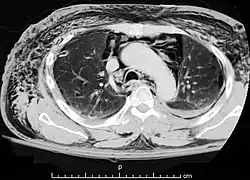

| A CT scan showing air in the mediastinum | |

Pneumomediastinum is uncommon and occurs when air leaks into the mediastinum. The diagnosis can be confirmed via chest X-ray showing a radiolucent outline around the heart and mediastinum or via CT scanning of the thorax.